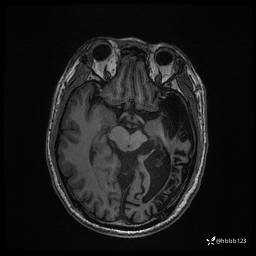

患者男,43岁。

简要病史:癫痫患者复诊,昨日发作5-6次,建议住院进一步治疗。

入院完善脑癫痫组合序列:

T2: